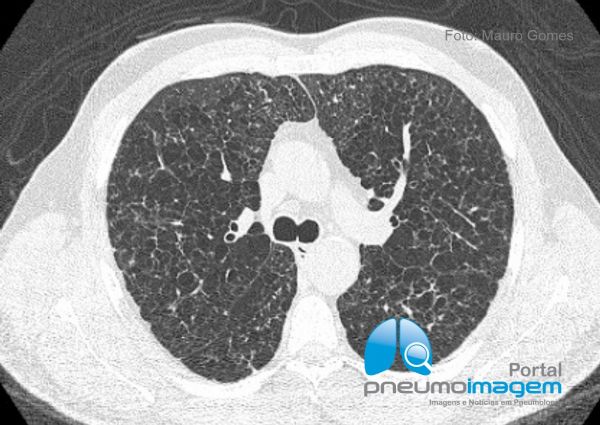

Comprometimento pulmonar da Histiocitose de Células de Langerhans caracterizado por pequenos cistos arredondados de paredes finas, bilaterais, de distribuição difusa e homogênea pelas regiões centrais e periféricas dos pulmões. Ainda há espessamento de septos interlobulares e discretas áreas em vidro fosco.

Pulmonary involvement of Langerhans cell Histiocytosis characterized by small round, thin-walled, bilateral cysts of diffuse and homogeneous distribution through the central and peripheral regions of the lungs. There is still thickening of interlobular septa and discrete ground glass opacities.

O achado mais frequente na Histiocitose de Células de Langherans são os cistos pulmonares, geralmente pequenos, mas que também podem assumir tamanhos variados. Em algumas situações as paredes dos cistos podem ser espessas e irregulares, o que não ocorreu nesse caso. A associação com nódulos pulmonares varia de acordo com a fase de evolução da doença (fases mais precoces) e esse achado auxilia na suspeita diagnóstica.

The most common finding in Langherans cell histiocytosis is pulmonary cysts, usually small but can also assume varying sizes. In some situations the walls of the cysts may be thick and irregular, which did not occur in this case. The association with pulmonary nodules varies according to the stage of evolution of the disease (earlier stages) and this finding helps in the diagnostic suspicion.